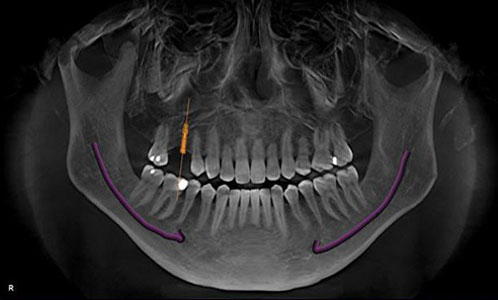

Implant Planning Prior to Placement

Our state of the art 3-Dimensional Imaging allows us the advantage of implant planning prior to placement.

The most ideal site, based on the height and thickness of available bone, can be selected, as well as the most optimally sized implant fixture for that specific location before even putting drill to bone.

Giving both the patient and the surgeon peace of mind.